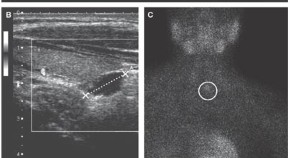

• Struma ovarii is a rare tumor, characterized by the presence of thyroid tissue in an ovarian teratoma. In this article Yassa et al. describe a patient who presented to her gynecologist with a pelvic mass, which was found to be a malignant struma ovarii. The investigations and treatment options for this tumor are described.